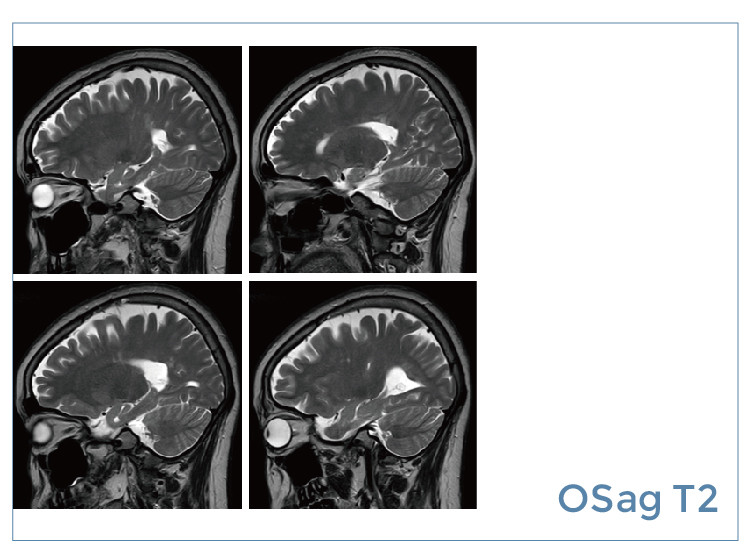

【朗润影像档案】磁共振影像病例分享(编号20190823)